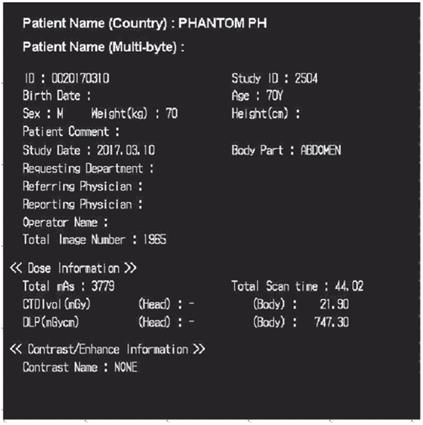

Часть персональных данных может быть закодирована непосредственно на участках изображений (например, в дозовых отчетах, вторичных объемных реконструкциях и др.), как показано на рисунке 2.

Рисунок 2 - Пример медицинского изображения с внедренной приватной информацией